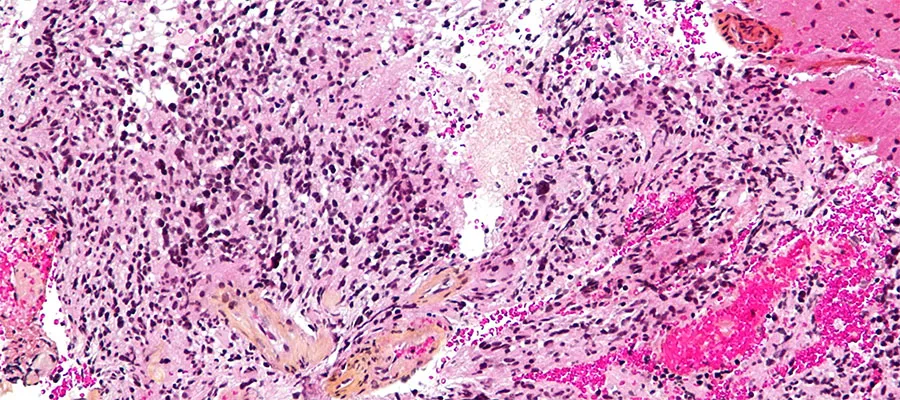

Histopathological section of a brain tumour.